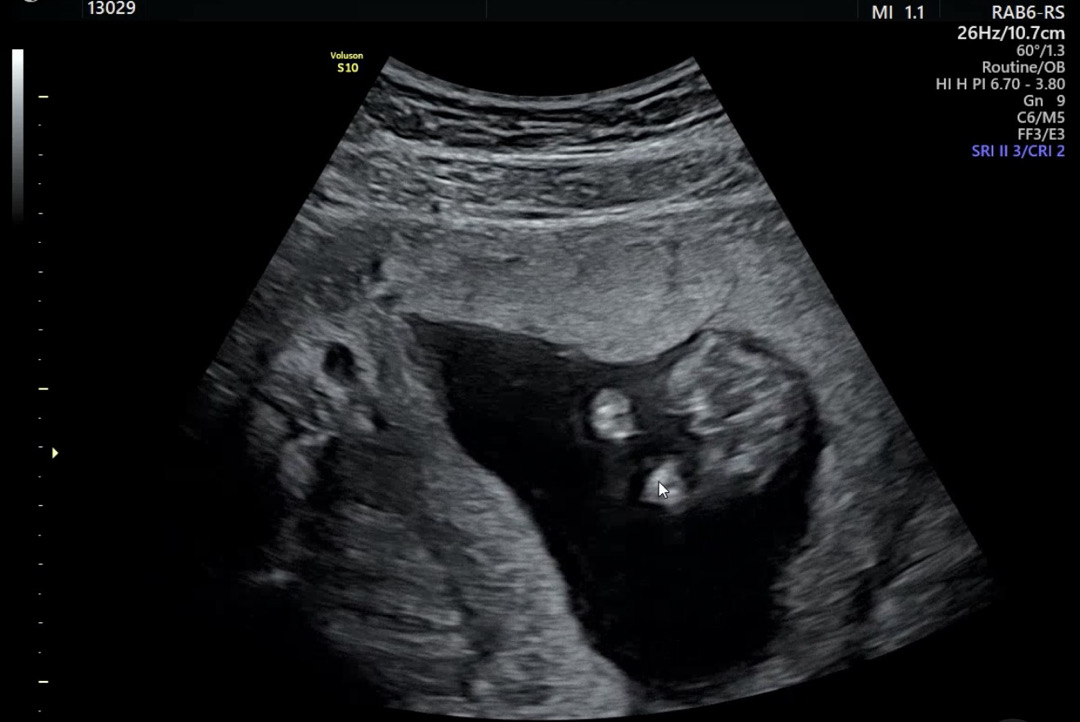

14주 5일 성별 예측..해주세요🩷

병원에서 90프로 확정이지만 16주까지 10%의 확률로 바뀔 수 있다는데 바뀌신 분들도 계실까요..? 친구는 탯줄 같다고도 하고… 성별 뭐 같나요..?(답정너 같네요….😂)